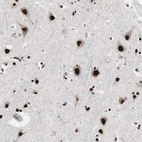

Immunohistochemical staining of human cerebral cortex shows strong nuclear positivity in neurons.